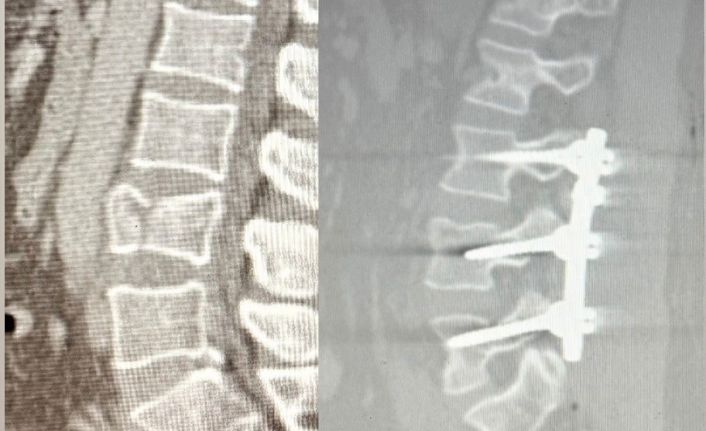

Patnos Devlet Hastanesi’nde ilk kez gerçekleştirilen lomber stabilizasyon ameliyatı sonrası, çökme kırığı yaşayan hasta kısa sürede ayağa kalktı.

Ağrı’nın Patnos ilçesinde 2,5 metre yüksekten düşen 41 yaşındaki Tekin Maskar, bel bölgesindeki kırık nedeniyle acil servise başvurdu. Yapılan tetkiklerde omurgada çökme kırığı tespit edilmesi üzerine hasta, ortopedi uzmanları Op. Dr. Muhammed Serpi ve Op. Dr. Mustafa İçen tarafından ameliyata alındı.

Ameliyat sırasında bel bölgesindeki omurların sabitlenmesini sağlayan lomber stabilizasyon tekniği kullanıldı. Hastane tarihinde ilk kez gerçekleştirilen bu operasyon sonrası hasta sağlıklı şekilde yürümeye başladı.